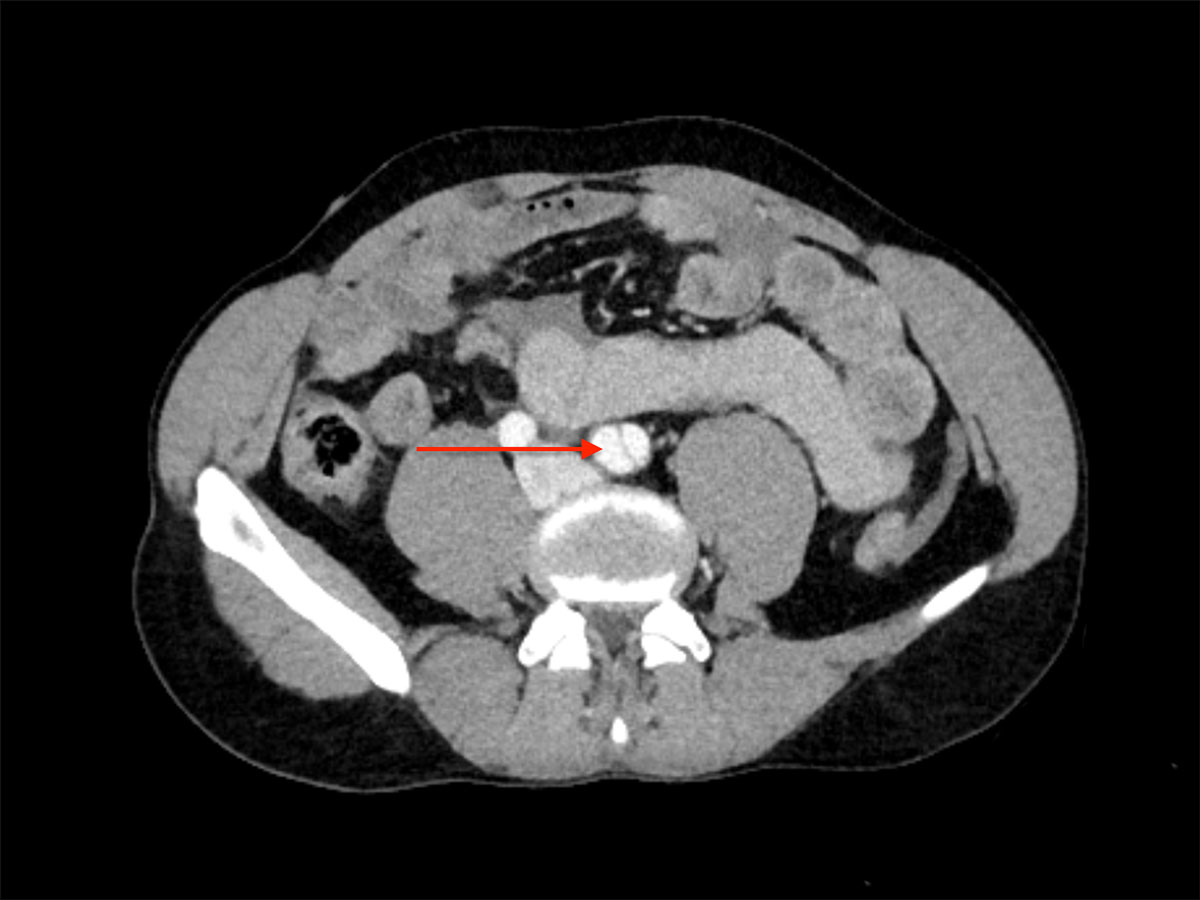

A 42-year-old male was admitted to our emergency department with acute abdominal pain, lipothymia and nausea. The patient was tachycardiac and hypotensive. Physical examination revealed signs of peritonitis. His bloods showed elevated lactates, at 4 mmol/l, while haemoglobin level was normal. The abdominal computed tomography (CT) angiography revealed a massive haemoperitoneum from a ruptured aneurysm of a distal branch of the ascending left colonic artery (fig. 1). Moreover, several aneurysms and strictures of the main intra-abdominal arteries were found, including dissections of both the superior mesenteric and the left common iliac arteries (figs 2 and 3 ).

Figure 3 Emergency abdominal CT scan displaying dissection of the left common iliac artery (arrow).